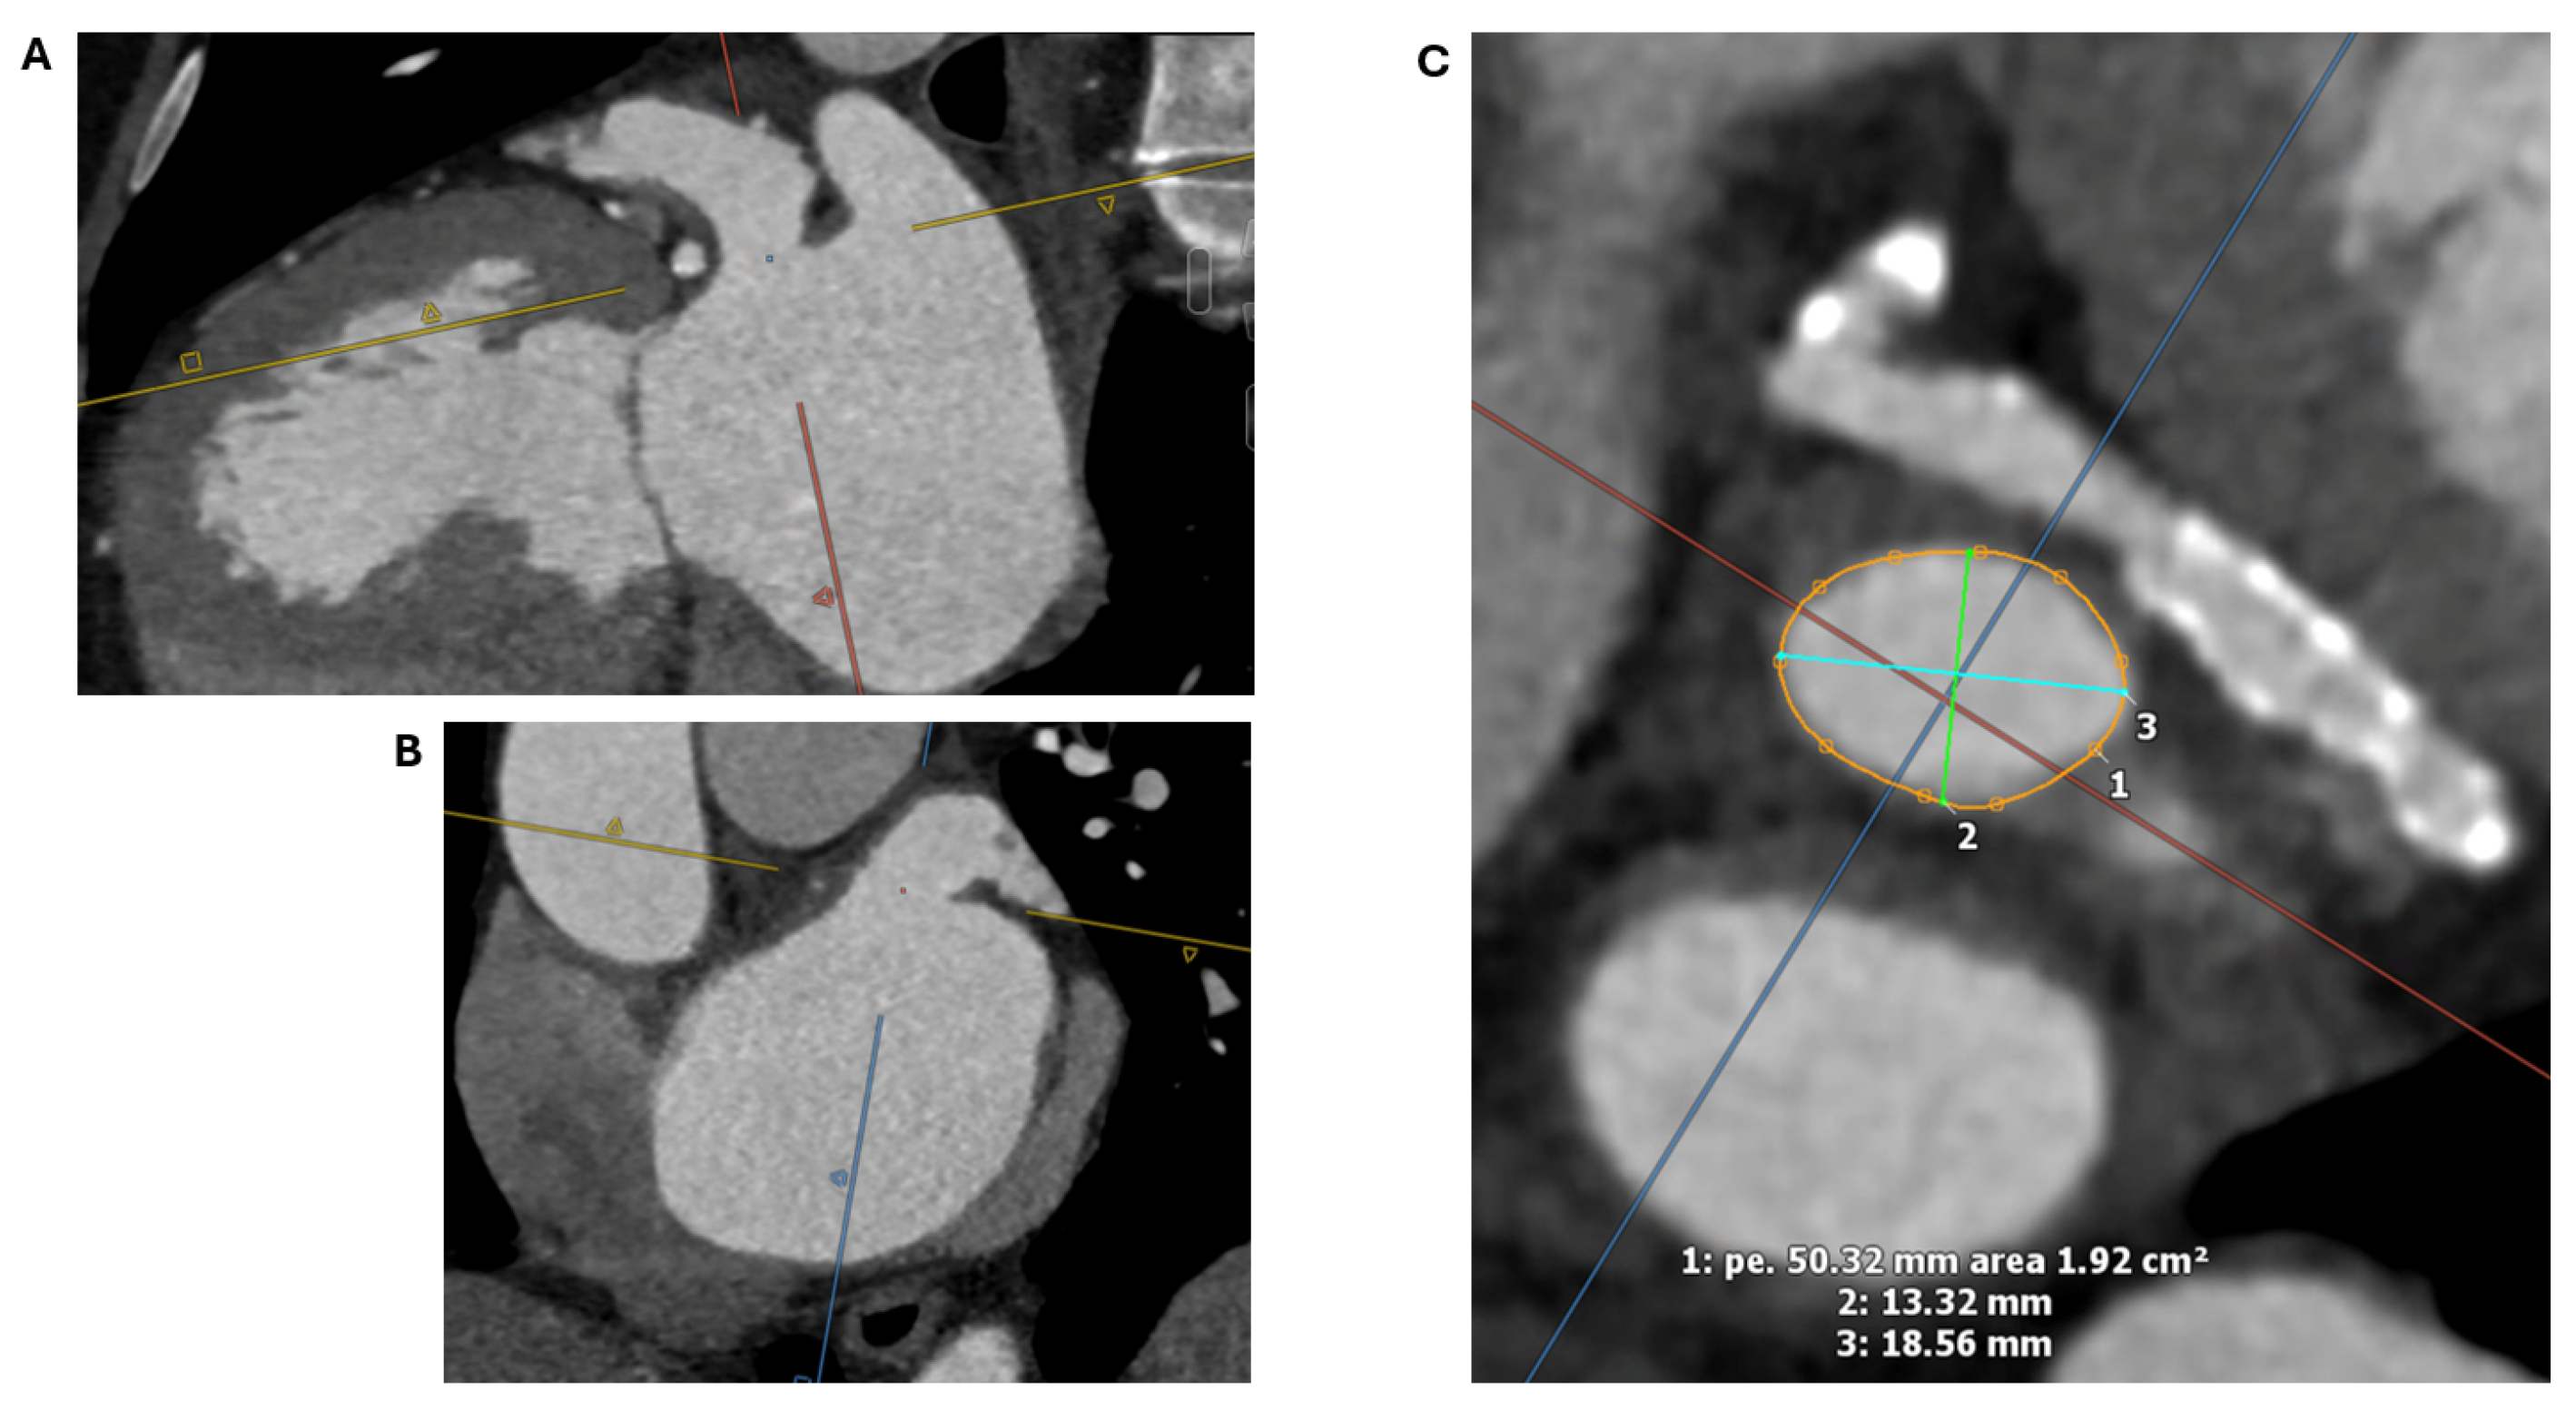

2.1.2. LAA Measurements

2.1.3. Assessment of the Inter-Atrial Septum

- Fukutomi, M.; Fuchs, A.; Bieliauskas, G.; Wong, I.; Kofoed, K.F.; Søndergaard, L.; De Backer, O. Computed Tomography-Based Selection of Transseptal Puncture Site for Percutaneous Left Atrial Appendage Closure. EuroIntervention 2022, 17, E1435–E1444. [Google Scholar] [CrossRef] [PubMed]

- Nelles, D.; Amli, H.; Sugiura, A.; Vij, V.; Beiert, T.; Nickenig, G.; Kütting, D.; Schrickel, J.W.; Sedaghat, A. The CT Derived Angle between the Transseptal Puncture Site and the Left Atrial Appendage as a Predictor for Complex Interventional Occlusion Procedures. Echocardiography 2023, 40, 1227–1236. [Google Scholar] [CrossRef] [PubMed]